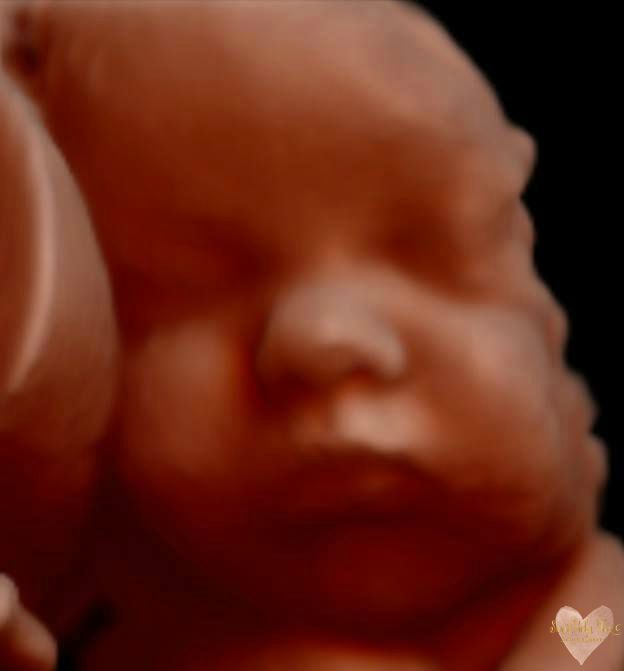

3D/4D/5D Ultrasound Gallery

Take a peek at our Photo Gallery. All of our 2D, 3D, 4D, HD elective ultrasound images are truly ours. They come directly off our machine from our highly trained staff. We can start getting great 3D/4D images as early as 10 weeks!